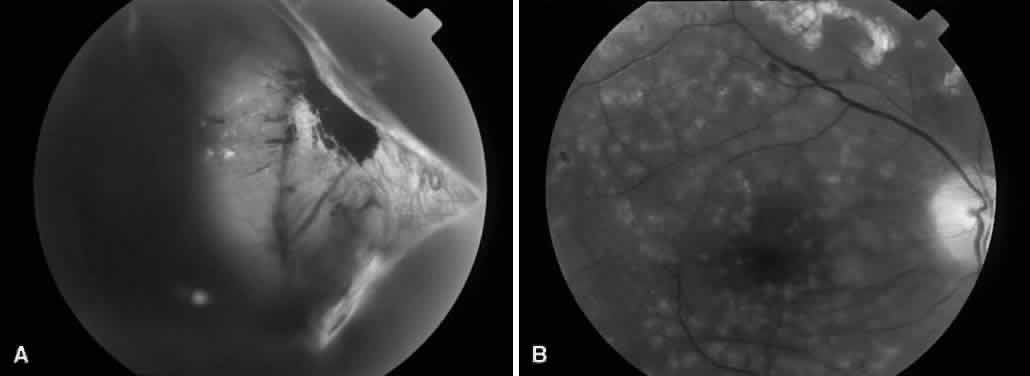

COMBINED TRACTION-RHEGMATOGENOUS RETINAL DETACHMENT

Fig. 5. A. Preoperative fundus photograph of an eye with combined traction-rhegmatogenous retinal detachment from severe proliferative diabetic retinopathy. B. Postoperative fundus photograph of the same eye after vitrectomy, membrane dissection (using delamination technique), and endolaser photocoagulation.